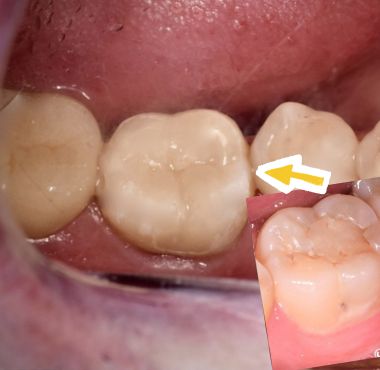

- Incrustaciones dentales

Son n tipo de restauración que se elabora de manera indirecta para ser cementada sobre la pieza dental, es la mejor opción cuando la perdida de estructura es muy grande y un restauración directa no es recomendable.